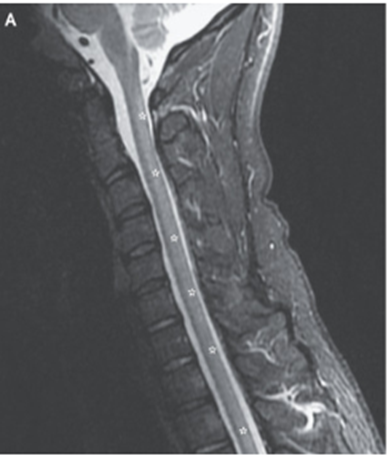

MRI施行。T2強調画像にてC1~Th12までの後部脊髄に高信号が示された。

水平断ではT2強調画像とFLAIRにて脊髄後索に高信号を認めた。

これは亜急性複合変性症で見られる「逆Vサイン」として知られる所見。